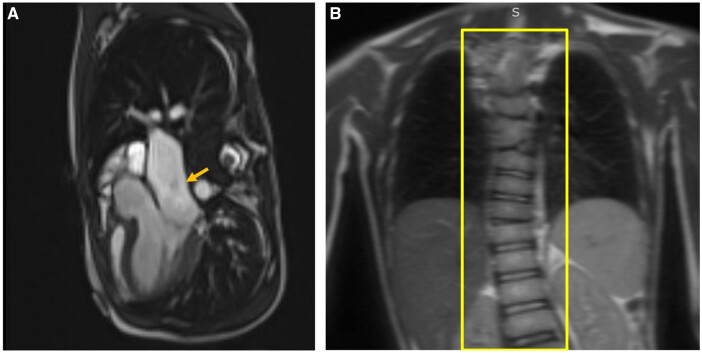

This case report highlights vertebral segmental anomalies and the fact that the child presented has a rare neurologic condition called pontine tegmental cap dysplasia. Additionally, this case aims to educate learners in developing a differential diagnosis for vertebral and cardiac anomalies such as VACTERL syndromes and common syndromes associated with butterfly vertebrae in children and adolescents.